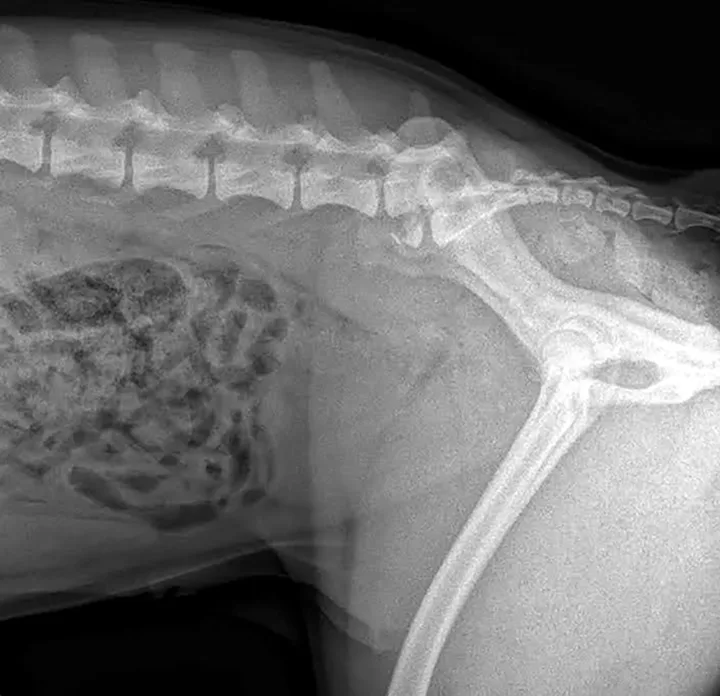

Survey radiography of the lumbar spine, pelvis, and hips is recommended. Common abnormalities identified in patients with LS disease include vertebral spondylosis, sclerosis of the vertebral end plates, and collapsed L7-S1 disk space. Stress radiography may exacerbate a lumbosacral step, which can further aid in diagnosis. Radiographs are also recommended to help rule out metastatic disease, diskospondylitis, trauma, or luxation (Figures 1-3).

Figure 1

Right lateral radiograph of a dog demonstrating L7 fracture. Images courtesy of Dr Tammy Stevenson.